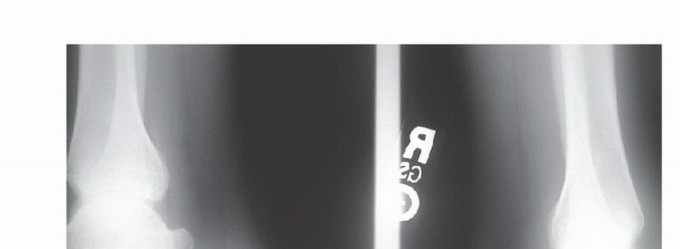

DEFINITION Spontaneous Achilles tendon ruptures are defined as a partial or complete loss of continuity of th…